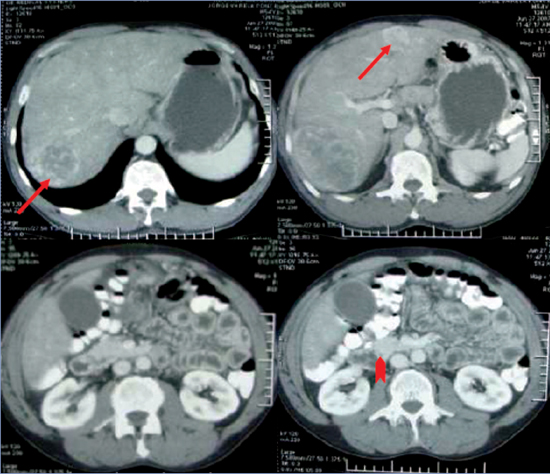

Se realizó Tomografía Computarizada (TC) de abdomen y pelvis con contraste que mostró numerosas lesiones nodulares hepáticas con características de "hemangiomas": una lesión en segmento VII de 9,3 cm, otra en segmento V de 3,5 cm, dos lesiones en segmento II de 3,3 cm y 5,7 cm, y otra en segmento IV de 1,8 cm; además colelitiasis y masa en mesenterio a derecha que comprimía un asa de intestino delgado sin plano de separación, sugerente de neoplasia de intestino delgado (Figura 1).

Figura 1. TC abdominal con contraste que revela la presencia de múltiples lesiones nodulares hepáticas (flechas) y una masa que engruesa el mesenterio y reduce parcialmente el lumen del íleon terminal (punta de flecha).